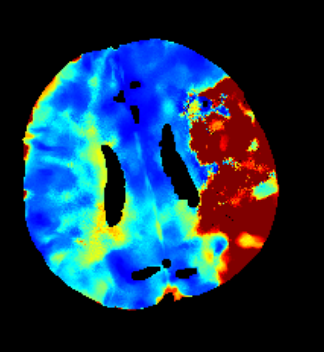

Des Weiteren ist mRay in der Lage eine Verarbeitung von Bildern durchzuführen und so Veränderungen bzw. Anomalien in Geweben zu finden, zu visualisieren und zu quantifizieren. Das Bildverarbeitungsmodul mRay VEOcore kann verwendet werden, um Bilder des Gehirns von Bildgebungsmodalitäten wie CT, Perfusions-CT oder MRT mit diffusionsgewichteter Auswertung (DWI) zu prozessieren. Als Ergebnis werden Kontrastveränderungen über die Zeit als farbige Perfusionskarten angezeigt, dies beinhaltet auch flussbasierte Parameter und Gewebeblutvolumen Berechnungen.

Die Perfusionsanalyse von Aufnahmen des Gehirns ermöglicht die Darstellung und Quantifizierung von minderdurchblutetem Gewebe (Penumbra), nicht-durchblutetem Gewebe (Kerngewebe) und dem Mismatch-Ratio zwischen den beiden Werten. Die berechneten Werte können der Unterstützung bei einer Entscheidungsfindung dienen, die auf der Beurteilung des Ausmaßes der Schädigung von Geweben basiert.